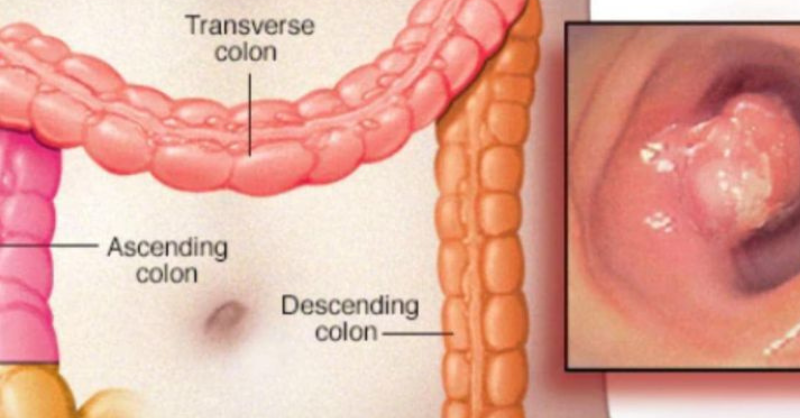

Stomach Can.cer (Gastric Can.cer): Symptoms, Causes, and Treatment

Stomach cancer, also known as gastric cancer, is a serious illness that affects many people worldwide. Understanding its symptoms, causes, and available treatment options is essential. Early detection...

Oral Can.cer: Symptoms You Shouldn’t Ignore.

Mouth cancer is a serious health concern. It refers to various types of cancer that affect the tissues of the mouth, including the lips, tongue, floor of the...

If you see 8 signs, go for an early check-up

Cancer is often silent in its early stages, making it challenging to identify without noticing subtle changes in the body. One area many people overlook is their bathroom...